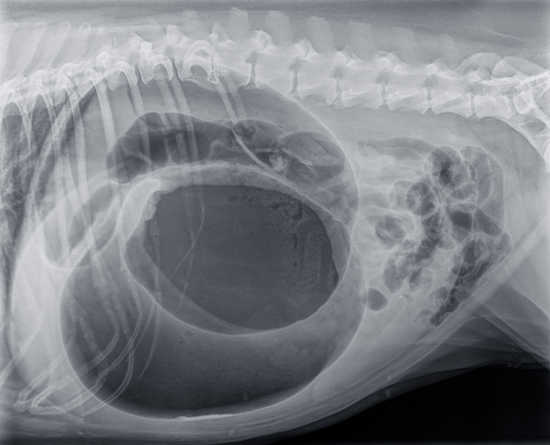

kép: gyomorcsavarodás kutyáknál